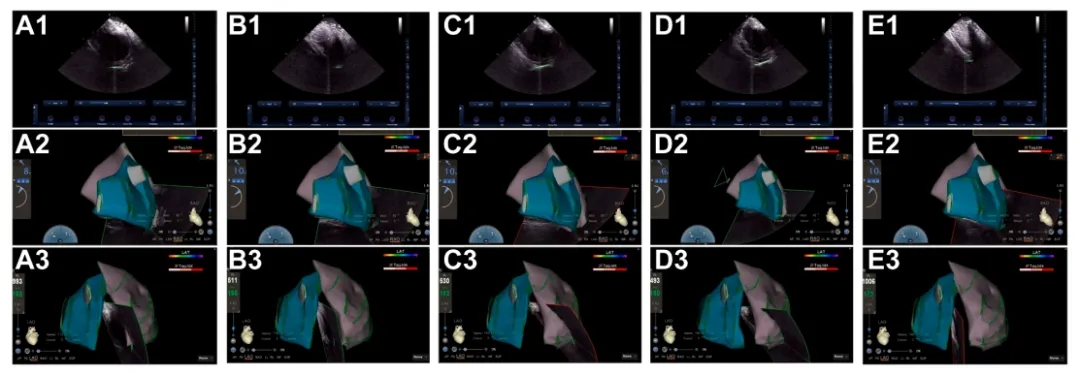

➤单极导线连接到穿刺针的远端,通过与CARTO三维标测系统集成实现实时可视化。

(A)血管专用穿刺针;(B 至 D)定制电缆的“a”端连接到针的尾端,而“b”和“c”端连接到CARTO系统的PINBOX。